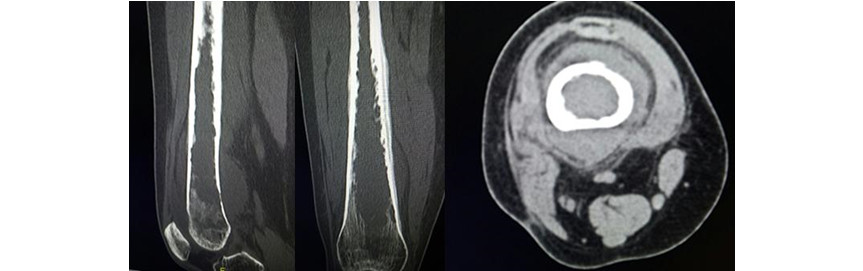

Volver a los detalles del artículo Sarcoma sinovial con invasión medular